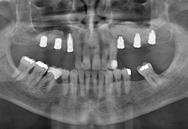

Estudios radiográficos de inicio

En la radiografía lateral de cráneo (Figura 4) se ve la aparatología con la que llegó la paciente, el perfil es convexo, hiperdivergente y las vías aéreas permeables.

En la radiografía panorámica (Figura 5) se observan en 20 dientes los brakets viejos, en los molares 16, 27 las bandas, el canino 13 retenido en el paladar, el botón de Nance, la

ausencia de molares 26, 46. Elmolar 16 tiene un tratamiento endodóntico

Figura 3. Oclusal superior e inferior. Figura 4. Radiografía lateral de cráneo de inicio.

Figura 5. Radiografía panorámica de inicio. Figura 6. Progreso cierre de frente, derecha e izquierda. Figura 7. Frente sonrisa, perfil inicio y final.

En las radiografías panorámicas (Figura 11), en la comparación inicio el botón de Nance, en la final se ve sin el canino retenido, el paralelismo radicular, con la ligera perdida ósea con la que llegó la paciente en la zona antero inferior y cuadrante 4, al final continúa sin cambios.

Figura 11. Comparativa Rx Panorámica inicio final.